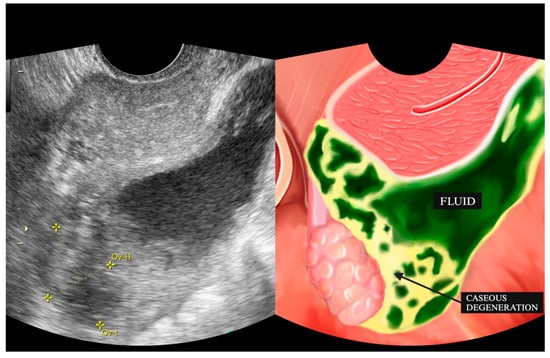

| 3 | IO (31) * | Caseous degeneration on the surface | Adhesion complex | Normal | Adhesion complex | Normal | (−) | Caseous degeneration on the surface of rectosigmoid colon and small bowel |

| 4 | SMK (29) * | Caseous degeneration on the surface. Complex fluid behind uterus | Normal | Not visualized | Adhesion complex with left fallopian tube | Hydrosalpinx | Complex fluid in cavum of Douglas with caseous degeneration | Caseous degeneration on the surface of rectosigmoid colon |

| 11 | Y (30) * | Normal | Adhesion to pelvic wall | Not visualized | Adhesion complex with left fallopian tube | Hydrosalpinx, filled with caseous degeneration inside | Complex ascites | (−) |